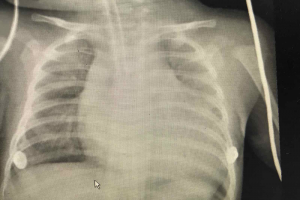

Vừa qua Bệnh viện Nhi Đồng Thành Phố tiếp nhận một trường hợp trẻ V. T. KH. 7 tuổi, nam, ngụ ở Đồng Tháp. Khai thác bệnh sử ghi nhận cùng ngày nhập viện, trẻ...